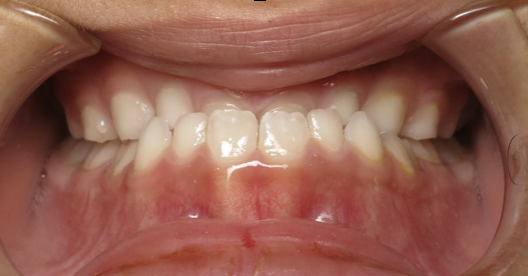

underbite corrected by expansion

Before

After